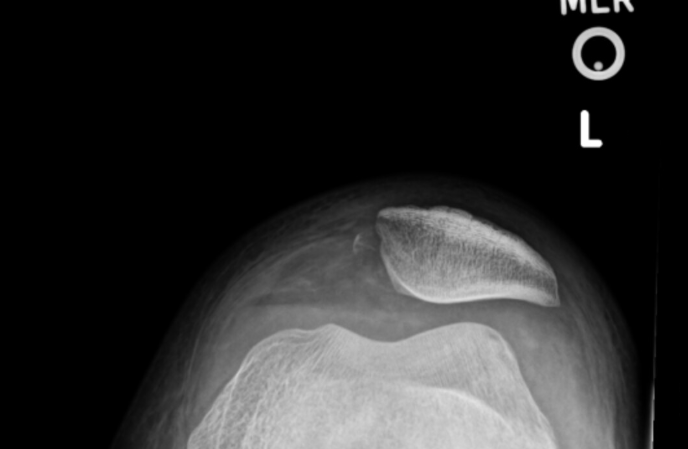

32-year-old male was doing a 425 lbs back squat and felt a painful “pop” in his anterior right knee above the kneecap and dropped to the ground. He has been unable to walk and his knee is extremely swollen. X-rays are read as normal but he cannot extend his knee on exam.

Knee Went Out